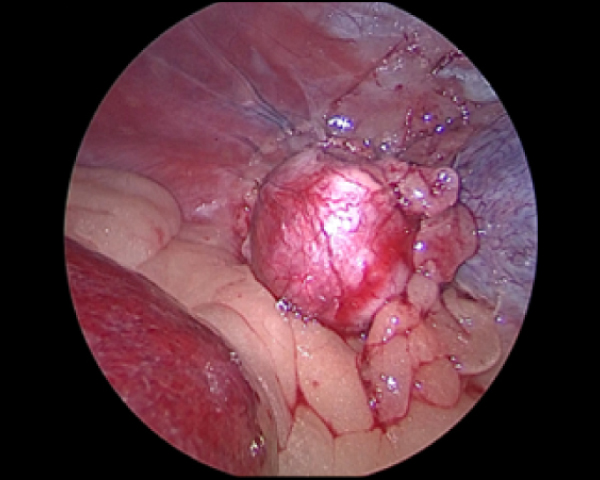

腹腔鏡を用いた副腎腫瘍摘出術